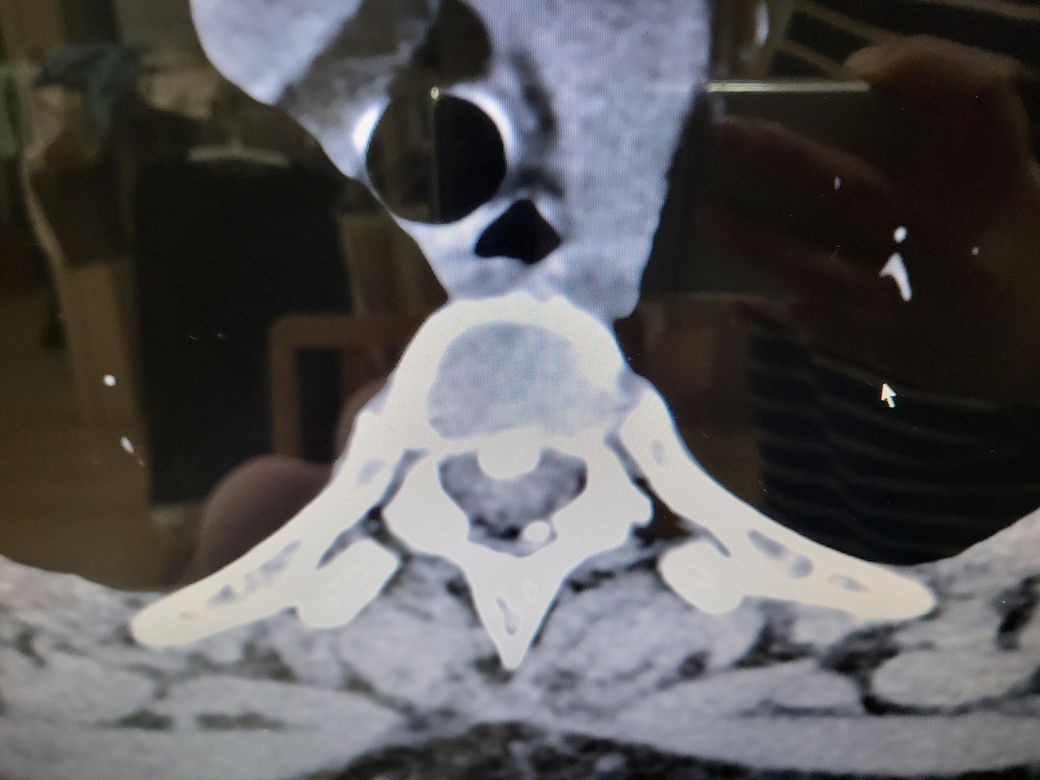

흉추 후종인대골화증 진단 받았습니다

흉추 2 3번 진단받았는데

• 2번 째 사진

흉추 2, 3번의 후종인대골화증(OPLL) 진단을 받았지만, 병원에서 약물 치료가 필요 없다고 한 것은 현재 신경을 심하게 압박하지 않거나 진행 속도가 느린 상태일 가능성이 큽니다. 일반적으로 흉추 2, 3번은 목이나 어깨보다는 상체 중심부(가슴, 등 쪽)와 관련된 신경을 담당하므로, 승모근과 날개뼈(견갑골) 쪽 통증과 직접적인 연관이 적을 수도 있어요.

그러나 목을 삐끗한 이후 증상이 심해졌다면, 경추(목뼈)나 주변 근육, 신경 이상 가능성도 고려해봐야 합니다

승모근과 날개뼈 주변 통증이 지속된다면 경추(목 디스크, 신경 압박) 문제나 근막통증증후군(MPS) 등을 의심해볼 수 있습니다.